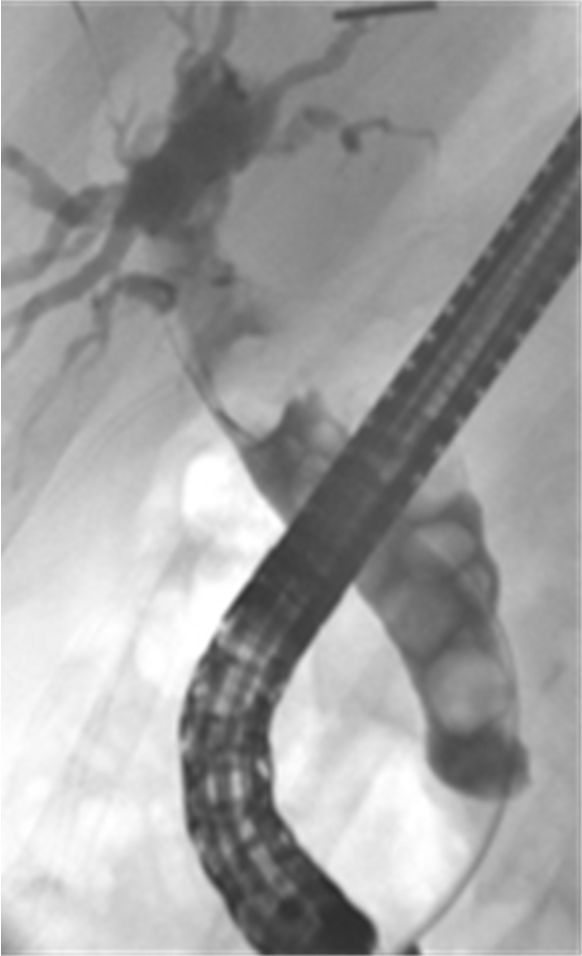

- Endoscopic retrograde cholangiopancreatography (ERCP) with stone extraction from the bile duct followed by laparoscopic cholecystectomy if the gallbladder containing stones.

Endoscopic retrograde cholangiopancreatography (ERCP)